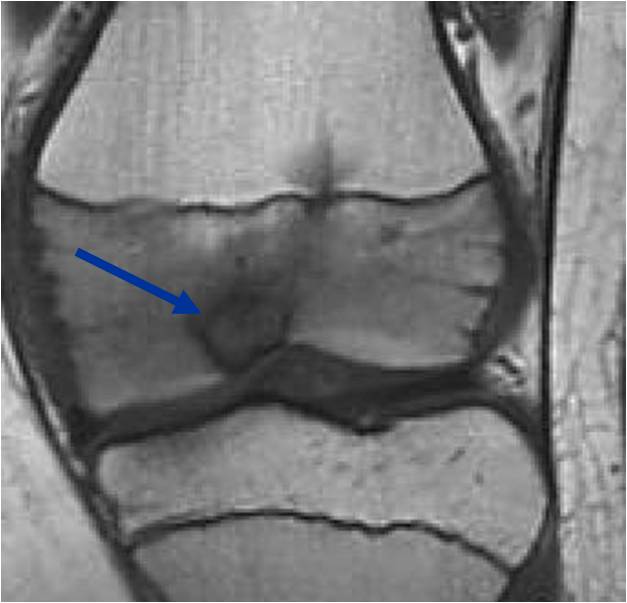

- (MRI appearance)

- Geographic, well circumscribed lesion in the epiphysis

- Intermediate Signal on T1

- High signal on T2 mixed with low signal areas (low signal areas proposed to be secondary to lysosomal content of highly cellular areas)

- Extensive Surrounding edema is common

- Joint effusion in 30-50% of cases